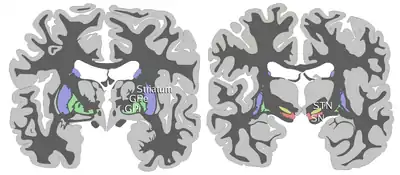

ROSTRAL: striatum, globus pallidus (GPe and GPi)

CAUDAL: subthalamic nucleus (STN), substantia nigra (SN)